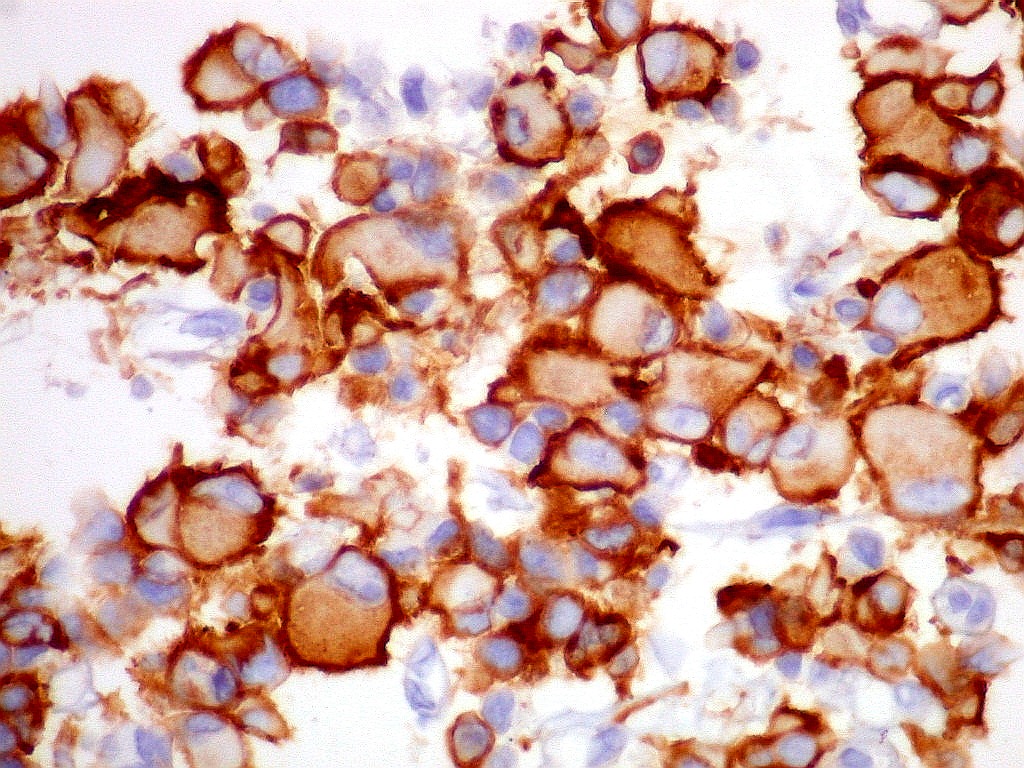

Sinaptofisina.     SNF, um marcador de neurônios, foi positiva no citoplasma em parte das células neoplásicas deste ATRT, enfatizando a expressão multifenotípica dos antígenos neste tumor.

Células  SNF negativas.

MAP2.   Microtubular associated protein,  marcador de diferenciação  neuronal. Universalmente positivo nas células deste ATRT.  Folículo linfóide  negativo (controle  interno).  Marcação é citoplasmática, na periferia do citoplasma.  Corpúsculo rabdóide negativo.  Para mais sobre MAP2, clique.

S-100.   Proteína S100 é expressa em células originadas da crista neural, como melanócitos e células de Schwann, e em macrófagos.  Aqui é observada em parte das células tumorais, em positividade nuclear e citoplasmática.